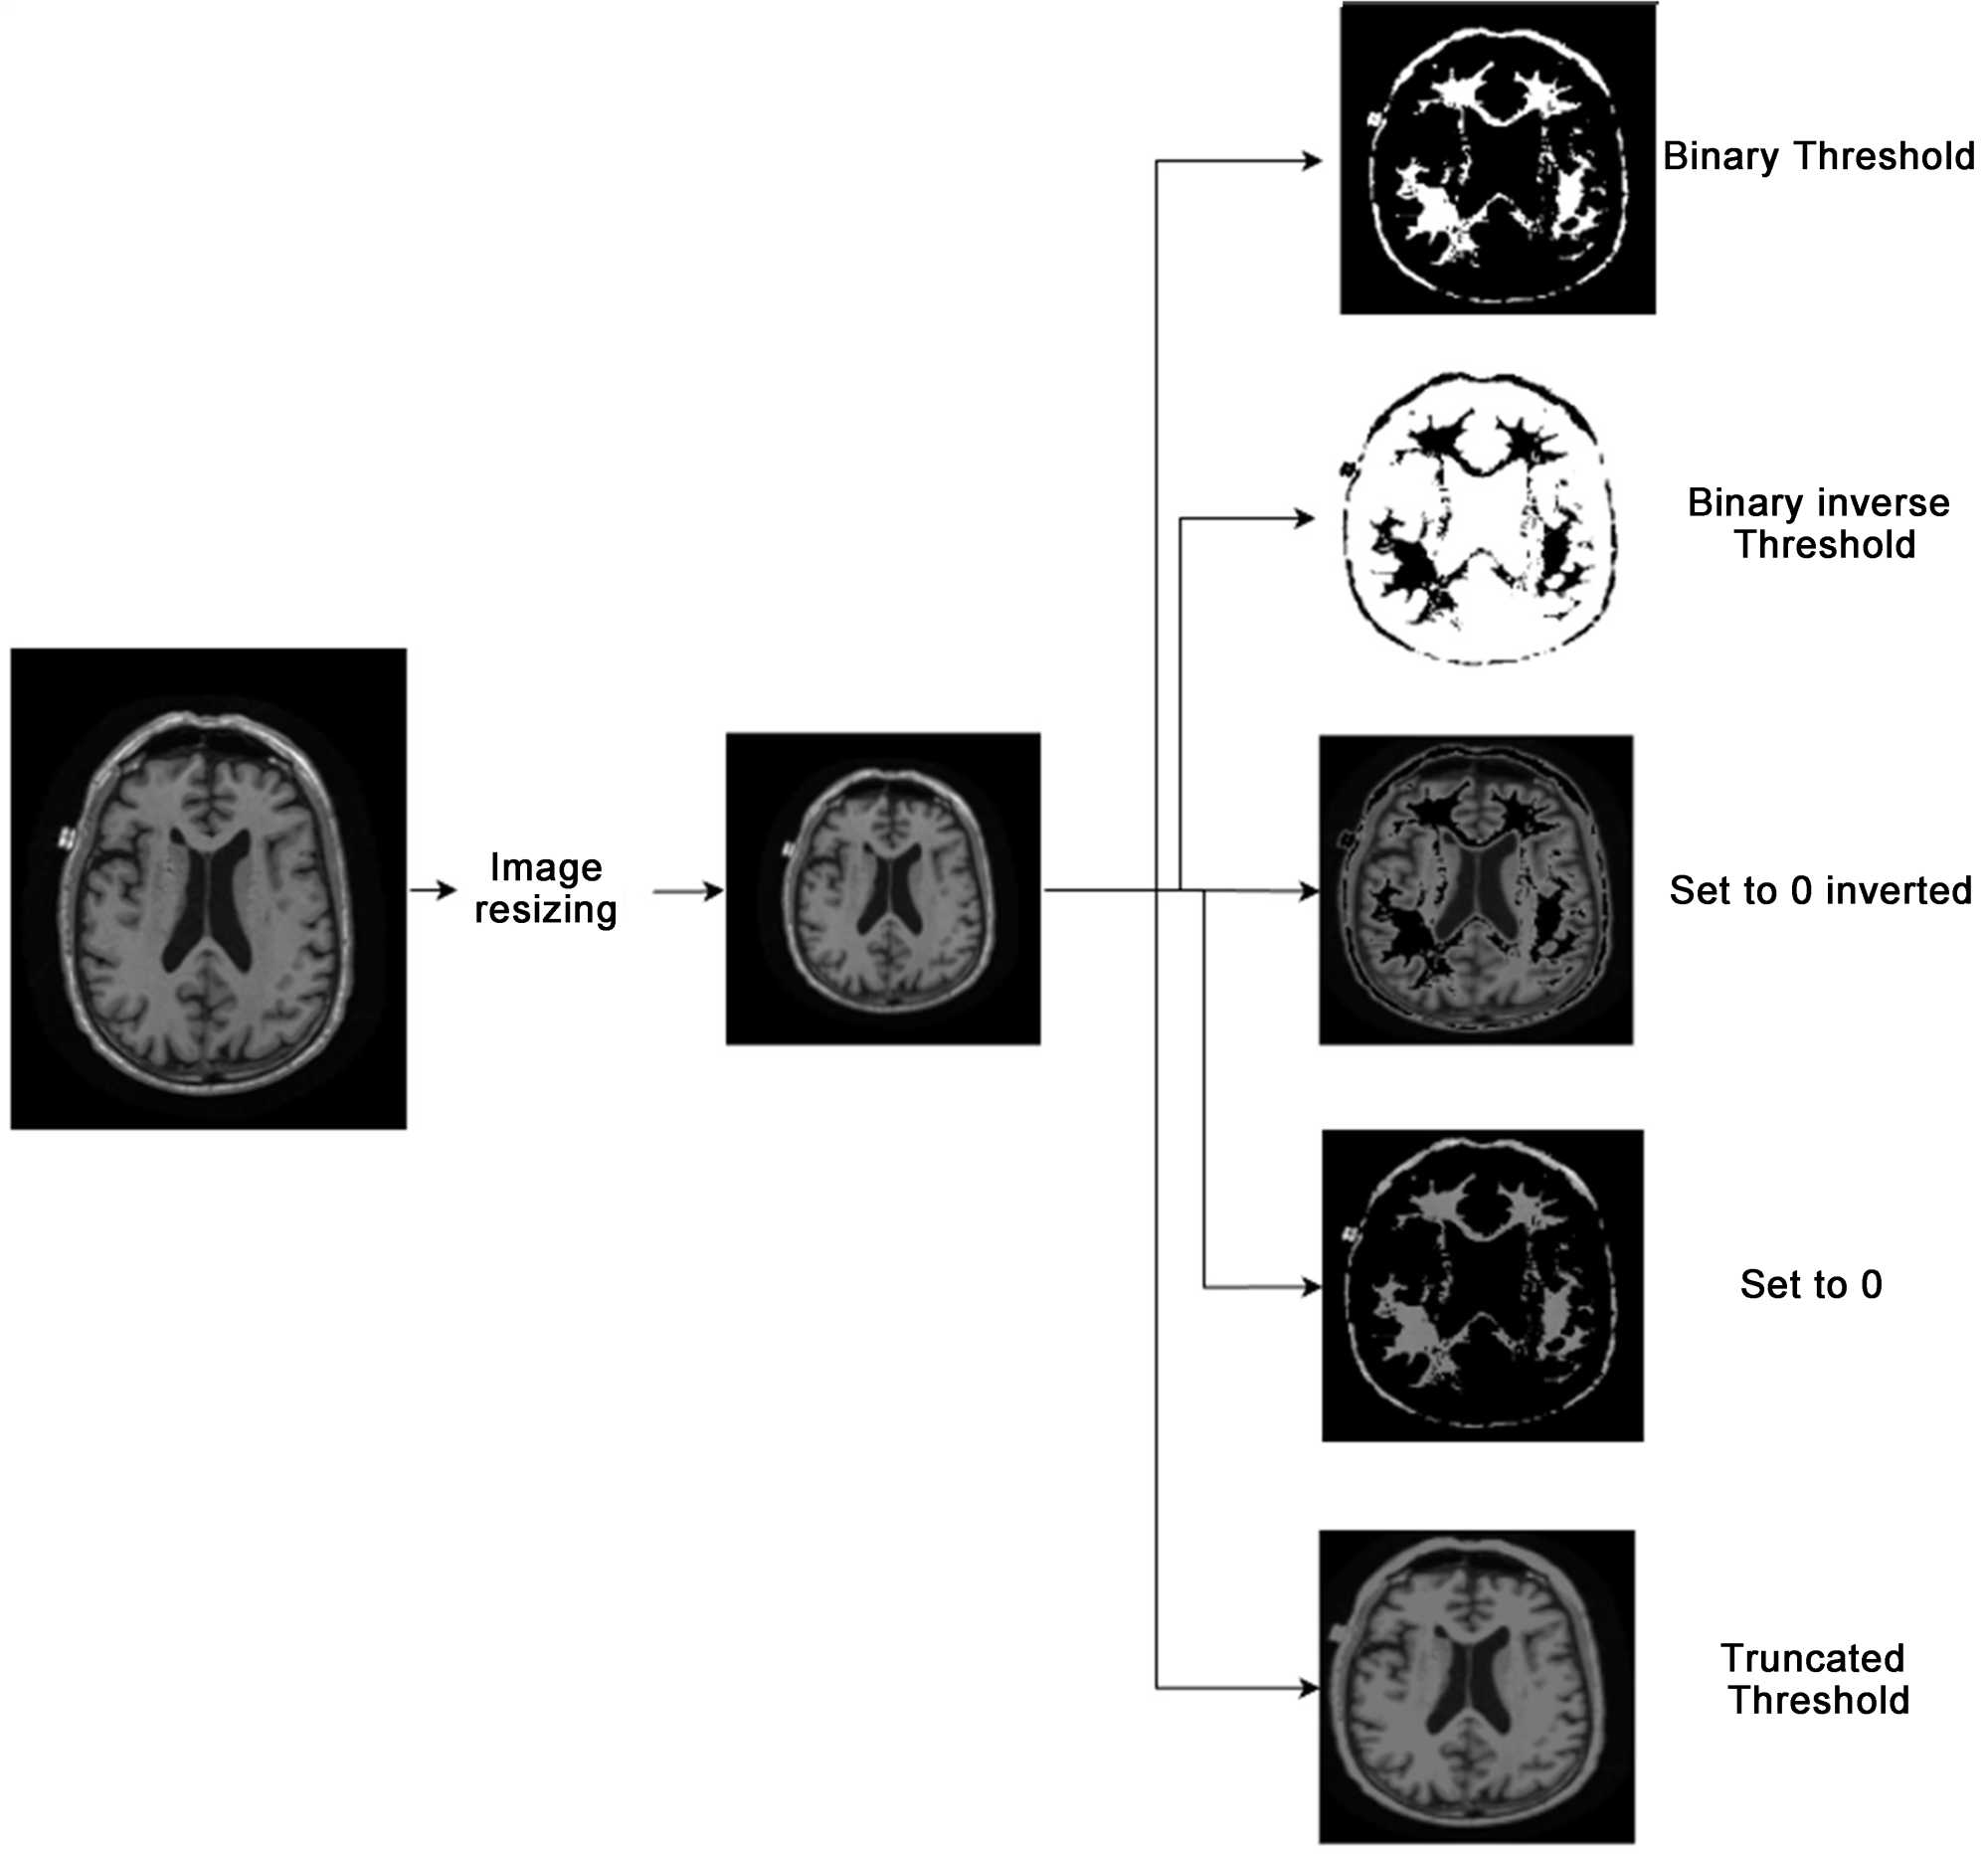

(Figure 6) depicts the watershed algorithm used over the dataset to segment the image and bring out the regions of focus. Six types of watershed algorithms were used, and the binary thresholding algorithm was selected.

Watershed algorithms employ binary thresholding to simplify segmentation. By transforming the grayscale image to a binary image, each pixel is assigned to the foreground (object), or background (non-object) based on a threshold value. Implementing a threshold is simple and effective. Hierarchical watershed techniques demand more marker identification and region merging. Complex image structures can be handled by these techniques, but they require more processing and parameter optimization. Basic picture segmentation using binary thresholding works well for items with obvious boundaries and background contrast. The simplicity, computational economy, and capacity to deliver good results in varied settings make this technique popular in image processing. Picture segmentation’s watershed algorithm depends on picture properties and task requirements.

Figure 6. Watershed algorithms applied.